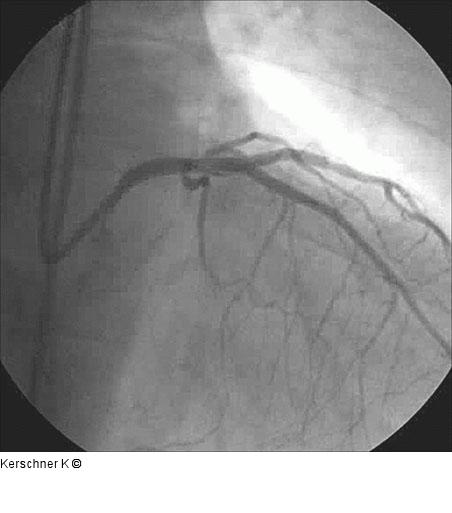

Abbildung 8: Ergebnis nach Crush Ergebnis nach Crush - RAO/kranial |

Abbildung 8: Ergebnis nach Crush

Ergebnis nach Crush - RAO/kranial |